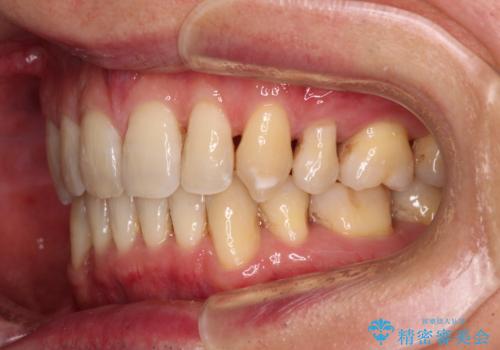

- 口元の閉じにくさと、前歯のでこぼこの歯並びを気にして来院された患者様です。

口元を積極的に引っ込めるために、上下左右の小臼歯計4本を抜歯することとしました。

叢生が強い場合、抜歯スペースが叢生を解消するために消費されるため、口元の突出感があまり改善されないことがあります。

今回の治療では、奥歯が前方に傾斜した歯並びだったため、奥に起き上がることで歯列が後方に移動し、横側からも口元が引っ込んだ感じが分かるほど改善されました。